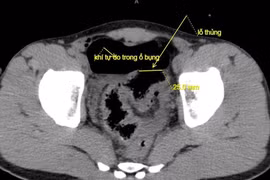

Ngày 25/11, thông tin từ Trung tâm Y tế Anh Sơn cho biết, các y bác sĩ vừa phẫu thuật lấy dị vật là chiếc tăm ra khỏi đại tràng của một người phụ nữ 66 tuổi.